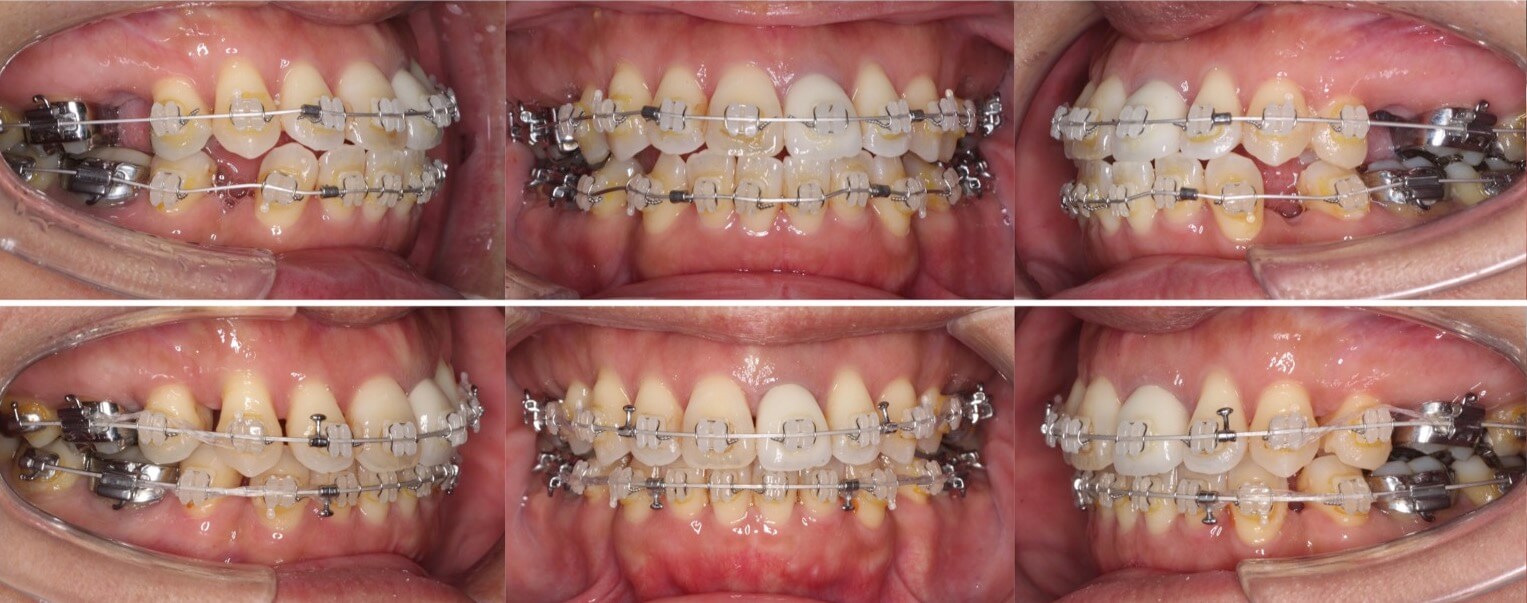

43歳女性・唇側矯正装置・抜歯

ミドルエイジの矯正治療で抜歯方針を選択する場合は、細心の注意を払います。これは、前歯が後方に引き下がりすぎる可能性があるからです。事前に横顔のシミュレーションを確認していただき、ほうれい線が深くなるなどのリスクも承諾の上、治療を開始しました。治療後はバランスの良い横顔になりました。

<症例概要>

主訴:口元の突出

年齢・性別:43歳女性

住まい:千葉県八千代市

症状:上下顎前歯唇側傾斜・正中離開

治療方針:上下左右4番(計4本)

治療装置:唇側矯正装置

固定装置:ナンスホールディングアーチ

治療期間:2年9か月

リテーナー:上下フィックス+プレートタイプ

治療費用:968,000(税込)

代表的副作用:痛み・治療後の後戻り・歯根吸収・歯髄壊死・歯肉退縮

▶︎その他の副作用